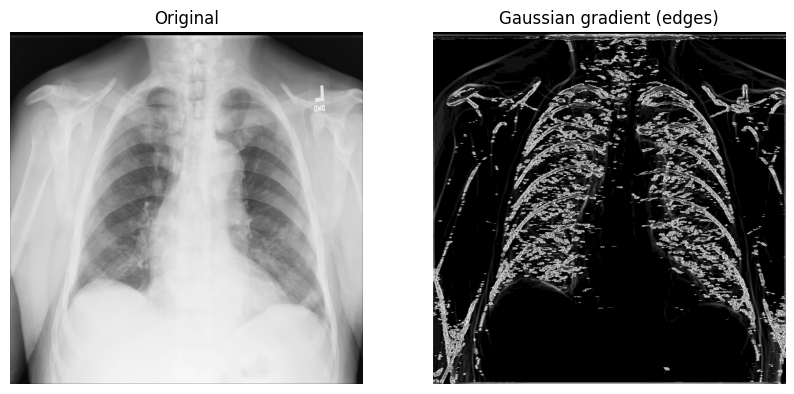

高斯梯度幅值法#

另一种有用的边缘检测方法是 高斯(梯度)滤波器。它使用高斯导数计算多维梯度幅值,并通过go除 高频 图像分量来提供帮助。

1.scipy.ndimage.gaussian_gradient_magnitude()

使用 sigma(标量)参数进行调用(用于标准差;您将2在下面的示例中使用):

x_ray_image_gaussian_gradient = ndimage.gaussian_gradient_magnitude(xray_image, sigma=2)

2.显示原始 X 射线和带有高斯梯度滤波器的 X 射线:

fig, axes = plt.subplots(nrows=1, ncols=2, figsize=(10, 10))

axes[0].set_title("Original")

axes[0].imshow(xray_image, cmap="gray")

axes[1].set_title("Gaussian gradient (edges)")

axes[1].imshow(x_ray_image_gaussian_gradient, cmap="gray")

for i in axes:

i.axis("off")

plt.show()